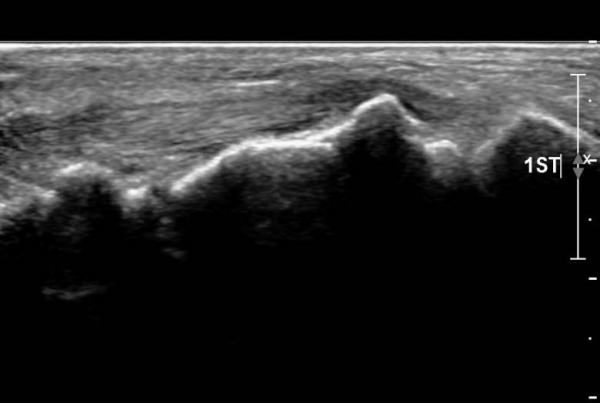

ŽÃËÀÚ¸¦ ¾à°£ ¹ß¹Ù´ÚÃøÀ¸·Î À̵¿ÇÏ´Ï ¼³Çü°ñ ºÎÂøºÎ°ÇÀÇ Àú¿¡ÄÚ º´º¯ÀÌ ¶Ñ·ÈÇÏ´Ù(»çÁø 3, 4).